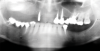

Fig 18. Panoramic radiograph at 20-year follow-up.

Figure 18

In 2020, the patient presented to the NYUCD Periodontology and Implant Dentistry Clinic. A clinical examination and radiographic evaluation showed that the patient's maxillary arch still exhibited good peri-implant soft-tissue health and stable marginal bone level with slight bone loss on implants Nos. 2, 6, 8, and 11 (Figure 18 through Figure 20). The maxillary prosthesis showed adequate stability with a slight chipped suprastructure on the porcelain on the right side. The patient was advised to substitute the implant-supported, screw-retained hybrid acrylic complete denture in the maxilla with a fixed, implant-supported, screw-retained prosthesis, which she declined due to financial considerations.